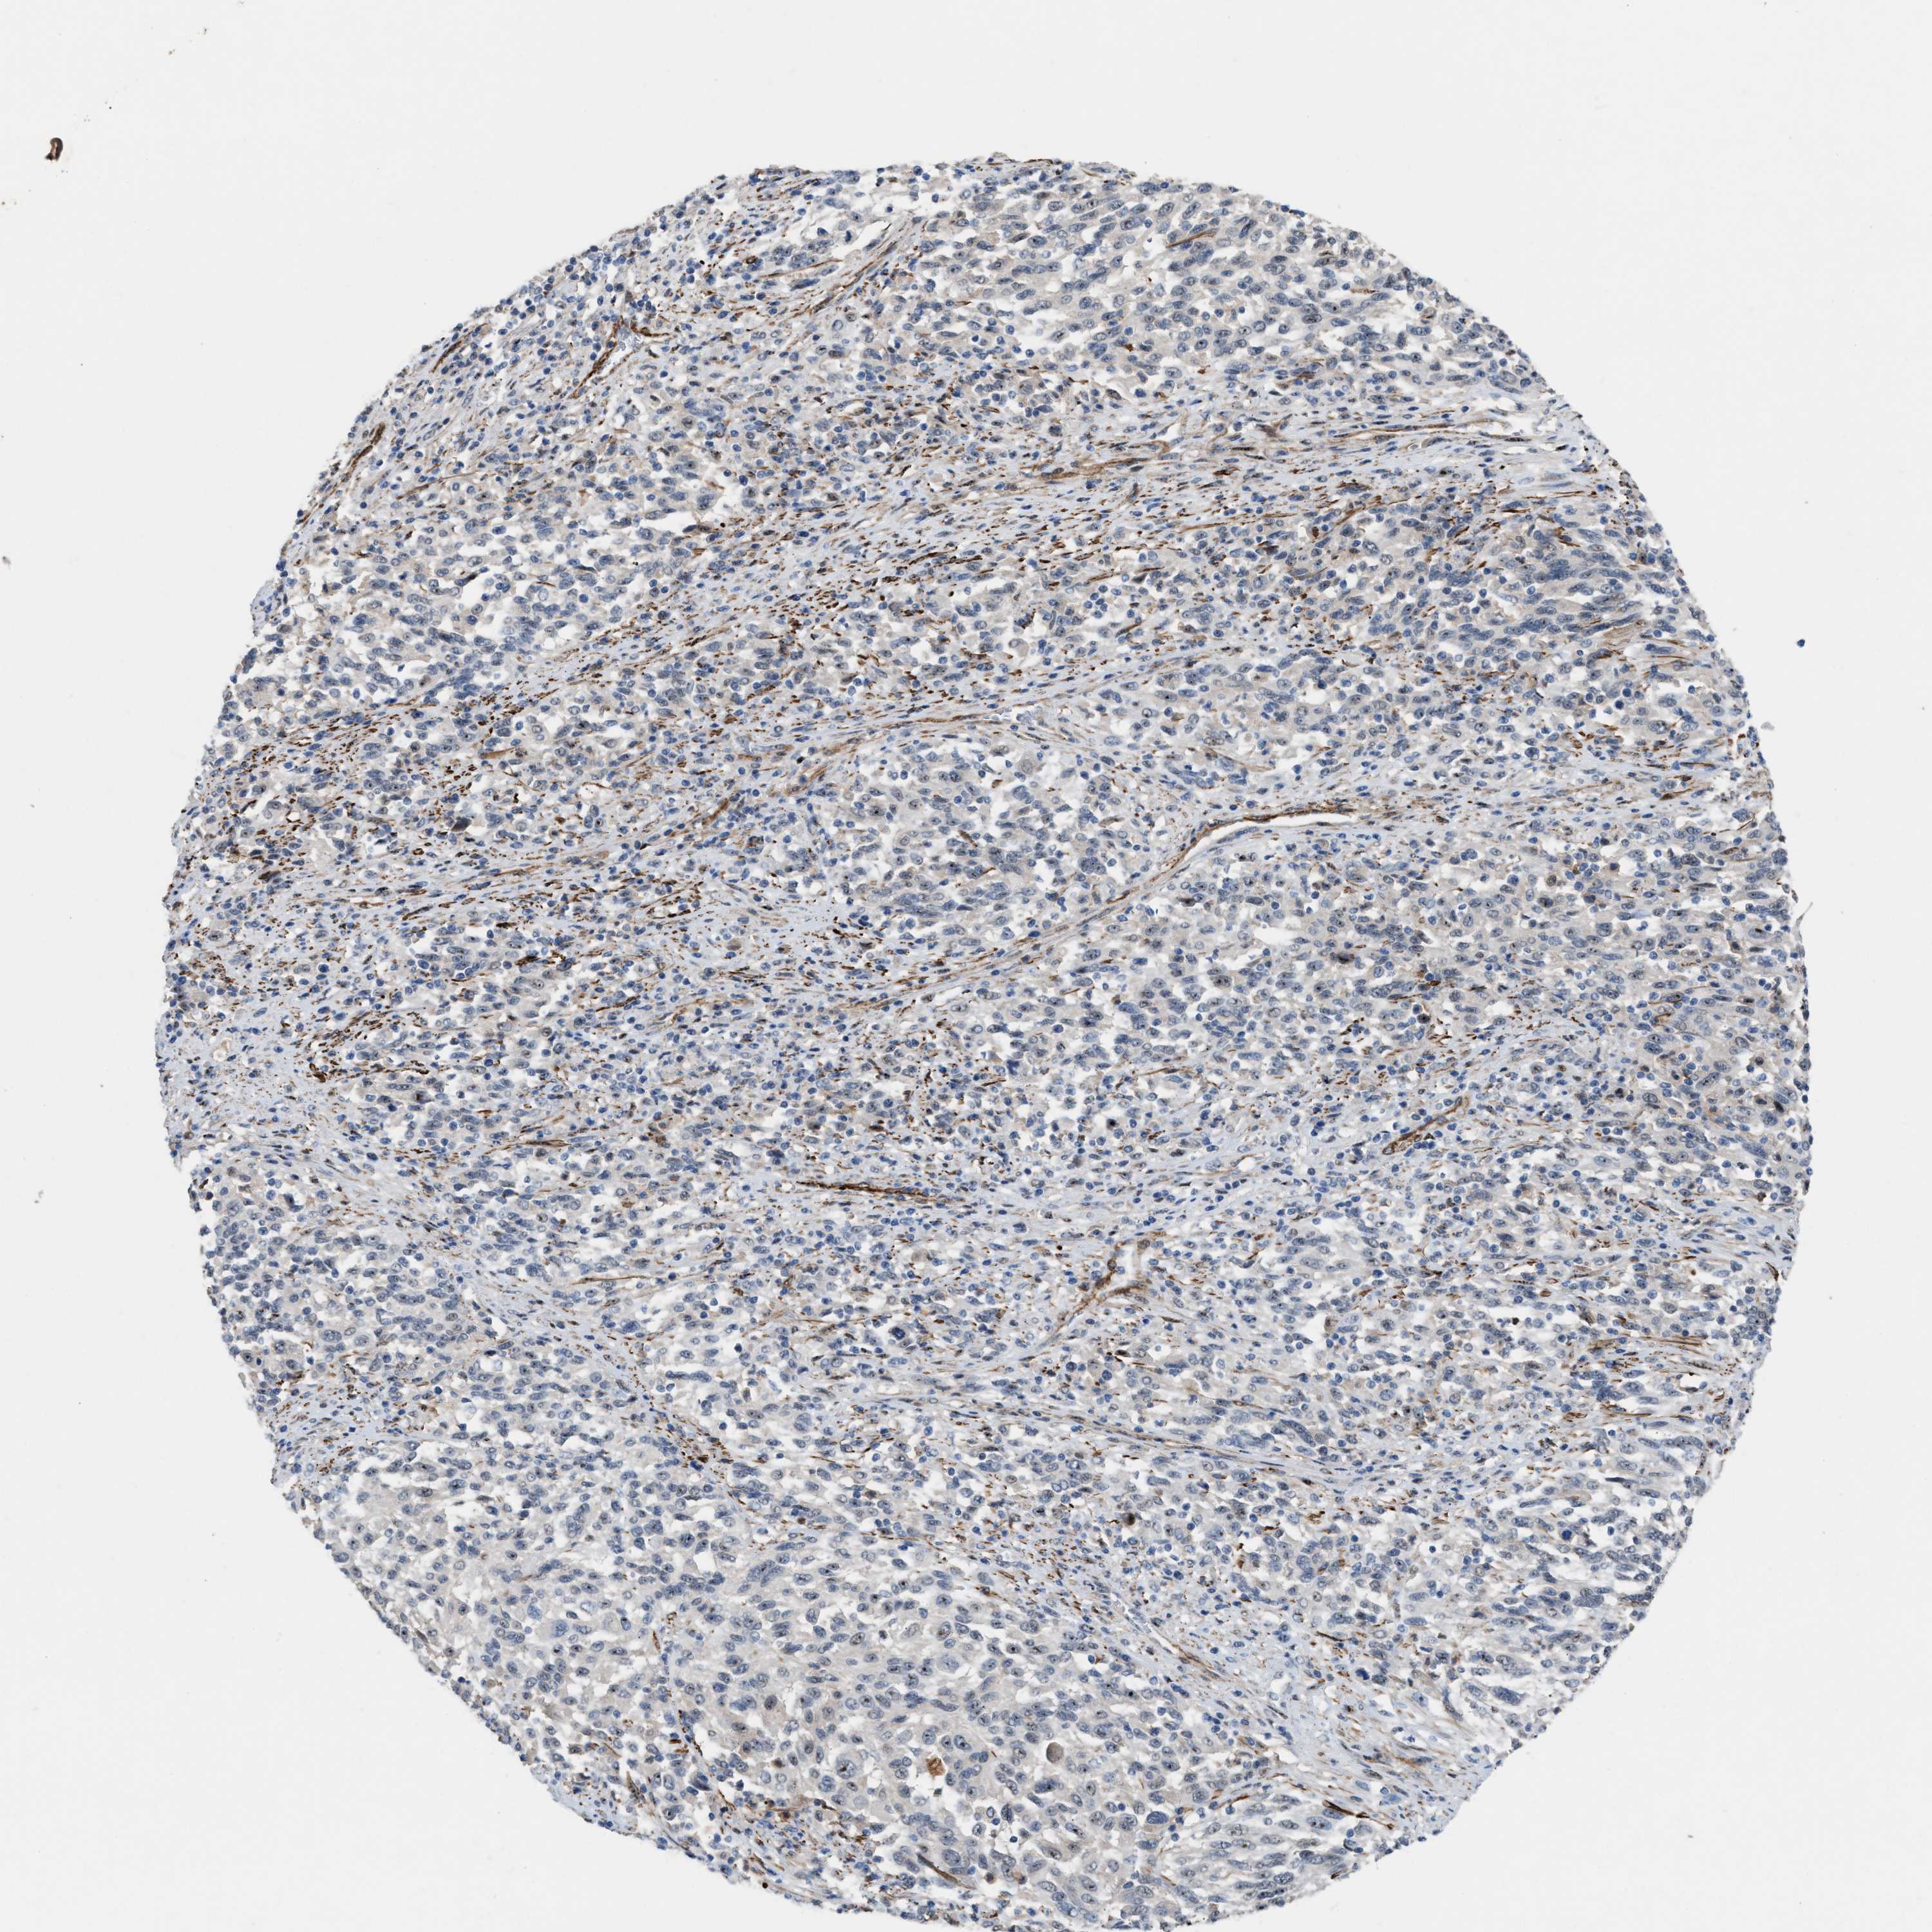

MELANOMA - Protein expressioni

A mouse-over function shows sample information and annotation data. Click on an image to view it in a full screen mode. Samples can be filtered based on level of antibody staining by selecting one or several of the following categories: high, medium, low and not detected. The assay and annotation is described here.

Note that samples used for immunohistochemistry by the Human Protein Atlas do not correspond to samples in the TCGA dataset.

Antibody stainingi

Antibody staining in the annotated cell types in the current human tissue is reported as not detected, low, medium, or high, based on conventional immunohistochemistry profiling in selected tissues. This score is based on the combination of the staining intensity and fraction of stained cells.

Each image is clickable and will lead to virtual microscopy that enables deeper exploration of all samples and also displays staining intensity scores, fraction scores and subcellular localization as well as patient and tissue information for each sample.

Antibody HPA021283

Antibody HPA021332

Staining

High

Medium

Low

Not detected

Intensity

Strong

Moderate

Weak

Negative

Quantity

>75%

75%-25%

<25%

None

Location

Nuclear

Cytoplasmic/membranous

Cytoplasmic/membranous,nuclear

Malignant melanoma, NOS

Malignant melanoma, Metastatic site